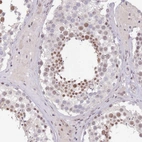

Immunohistochemical staining of human skin shows strong nuclear positivity in squamous epithelial cells.